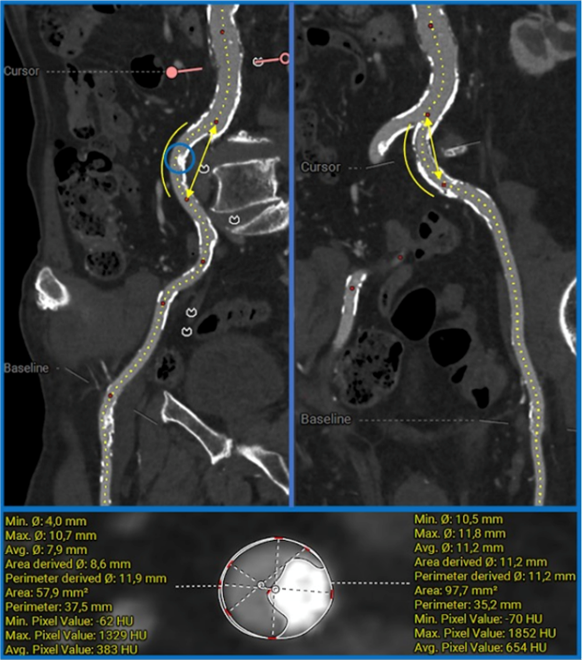

Preoperative CT scans were analyzed with a dedicated software (3Mensio, Structural Heart, Pie Medical Imaging) by trained analysts using the specific femoral access analysis package included with the software. All the included analysis were performed on contrast-enhanced CT scans.

MLD was first measured in both the left and right iliofemoral axes, and the largest vessel was chosen as the potential operative access. Patients were included if they presented a minimum Reference Vessel Diameter (RefD) of 5 mm, measured proximally to the tightest segment (where MLD was measured) in a healthy segment. After 3-dimensional (3D) reconstruction of the chosen axis, the analyst systematically performed the following measurements:

- Circumferential distribution of calcifications at the tightest site: once the MLD spot was identified, the distribution of the calcium along the cross-section circumference was graded according to degrees of its extension. Circumferential calcification was defined when at least 180º (Figure 1)

- Longitudinal distribution of calcifications: from the “stretched-vessel” view, using the filter for calcifications, the maximum length of the calcified wall across the entire diseased segment was measured as the percentage of calcium length over the vessel length (defined as diffuse calcifications when > 50%) (Figure 2).

- Vessel tortuosity: exploiting the “tangent angle” function, degrees of central line angulation proximal and distal to the MLD point were measured, obtaining a grade of the vessel curvature at the site of the MLD. Tortuosity was defined in the presence of at least 50º between the proximal and distal segments angles compared to the MLD site (Figure 2).

At the CT, the mean MLD was 4.4 ± 0.2 mm, with 4 cases presenting 1 spot with MLD less than or equal to 4.0 mm, and 2 cases presenting 2 sites less than or equal to 4.0 mm along the same iliofemoral axis (Table 2).

All cases presented at least a circumferential (≥ 180º) spot of calcium in correspondence of the MLD, while most of the cases presented diffuse calcifications spanning across the entire length of iliofemoral axis irrespective of the location of the narrowest spot (≥ 50% of diseased length of the vessel) (Figure 1B).

A tortuous segment at the level of MLD was identified in all cases, with 1 case (patient 11) also presenting a severely protruding speckle of calcium (≥ 50% of the lumen area) at the level of the right common iliac artery. (Figure 4).